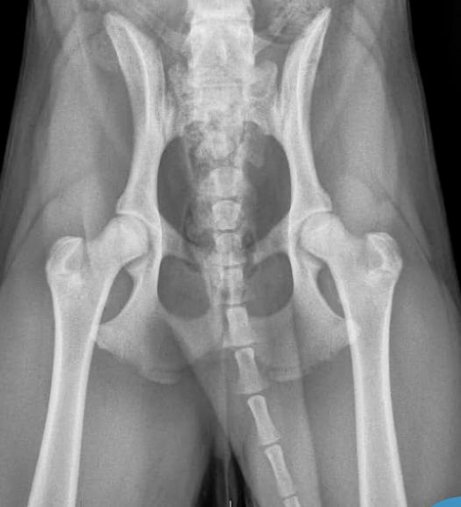

3. Was ist ein totaler Hüftgelenkersatz?

Bereits seit 1974 gibt es dieses vielfach erprobte und standardisierte Verfahren, bei dem ein fehlentwickeltes- oder stark geschädigtes Gelenk ersetzt wird. Alle Anteile des Gelenks werden hierbei durch synthetische/künstliche Materialen ersetzt. Dazu gehören die Beckenpfanne, der Oberschenkelkopf und der Oberschenkelhals. Aufgrund einer großen Vielfalt von anatomischen Gegebenheiten bei unseren tierischen Patienten, gibt es sehr unterschiedliche Implantattypen von denen manche in den Knochen geschraubt-, gehämmert oder einzementiert werden. Der Implantattyp wird bei der Voruntersuchung in jedem Fall einzeln festgelegt, um ein optimales Ergebnis zu erzielen.